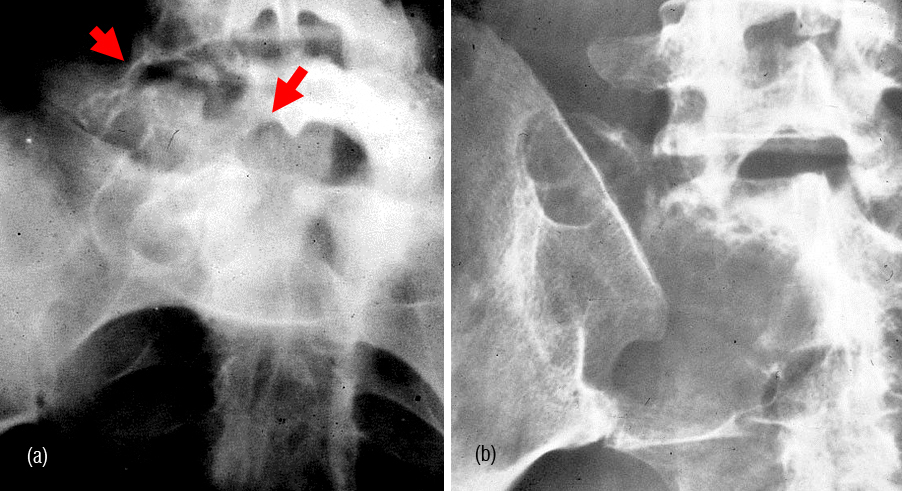

Radiologically, Sclerotic changes in the bone may be unifocal or multifocal. At times, lytic lesions may be also noted (Figure 8ab).

Figure 8: (a) Sclerotic myeloma – diffuse sclerosis of all the lumbar vertebrae. (b) Sclerotic lesion in the femur in Poems syndrome.

Primary lyphoma of bone is uncommon. However, when the bone is involved, radiological findings include both lytic and sclerotic changes with soft tissue swelling. In Hodgkin’s type of lymphoma sclerotic lesions predominate. Occasionally, only pedicles of the spine may be involved (Figure13abc).

Figure 13: (a) Lymphoma (Ivory vertebra) involving the body of L1. (b) Hodgkin’s lymphoma. Note the ivory pedicles. (c) Hodgkin’s lymphoma – conventional tomogram.